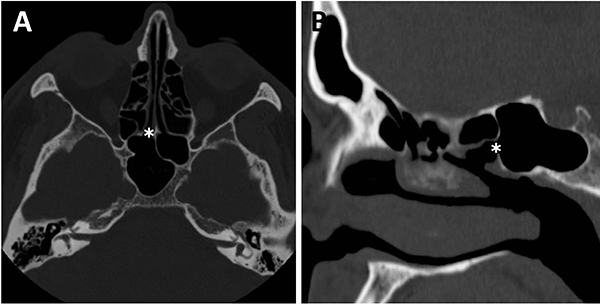

Respecto a los ostium esfenoidales, cabe destacar que son el punto de entrada óptimo al seno esfenoidal. En caso de ser dificultosa su localización (situación frecuente) se podría ingresar al seno esfenoidal aproximadamente 1,5 cm por encima del borde superior de la coana (fig. 11).23,13

El grado neumatización del seno esfenoidal se puede clasificar en selar, pre selar y conchal (fig. 12).1,29,30,58 En el tipo conchal, el área bajo la silla turca es de hueso sólido sin neumatización. En el tipo preselar, el área neumatizada no penetra más allá del plano perpendicular de la pared selar. En el tipo selar, presente en el 86% de los individuos, la región neumatizada se extiende al cuerpo del esfenoides bajo la silla turca, pudiendo extenderse hacia posterior. Esta característica del seno es importante ya que ante la presencia de un tipo conchal es recomendable la utilización de neuronavegación.23,58

Figura 11: Ostium esfenoidales identificables en TC. A) TC corte axial; B) TC corte sagital.

Figura 12: Neumatización del seno esfenoidal en TC cortes sagitales. A) Tipo selar; B) Tipo preselar; C) Tipo conchal.